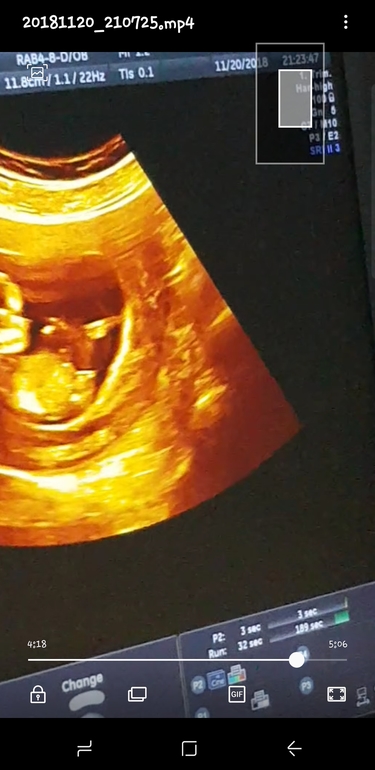

Боже, неужели у вас нет нормального снимка узи, которое дают почти всем? По снимку в посте не понять что к чему

Спасибо за ответ,просто на нашем узи малышь сидит,,и если его улржить как на вашем писюлька поднимется?!как вы считаете?

Помню, как я угол транспортиром меряла, в надежде, что он больше 30 градусов

... так надеялась на мальчика. Но как ни крути, девочка оказалась...

Думаю, что и у вас так же...Хотя видела фото как у вас у мальчиков, только писюлька подлиннее была.

Вам опять девочку обещают? Мне вот в 13,3 вообще даже не предположили пол и на фото не видно(. Сказали ждать 2 скрининга, а это ещё месяц! По Вашему фото не понимаю(.